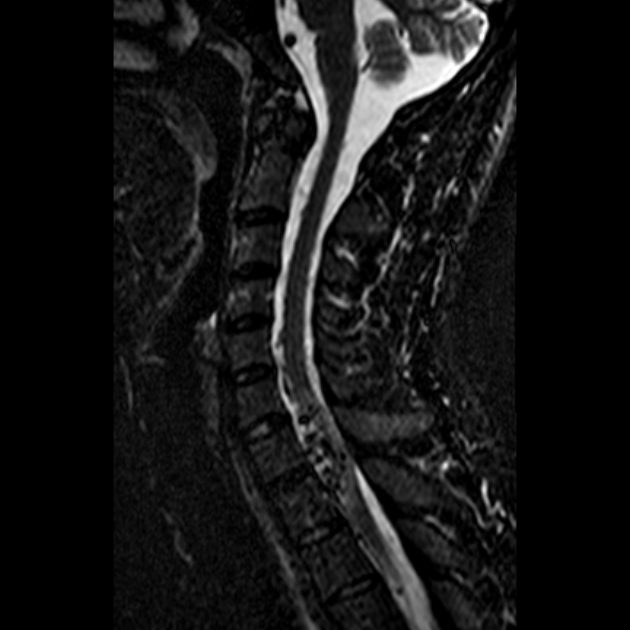

Магнитно-резонансная томография проводится в аксиальной, сагиттальной и корональной плоскостях с применением T1- и T2-взвешенных последовательностей, а также режимов с подавлением сигнала от жира и контрастным усилением. Применяется при подозрении на артериовенозные мальформации спинного мозга с целью выявления патологически изменённых сосудистых структур, оценки степени венозного застоя, признаков компрессии спинного мозга и вовлечения окружающих тканей. Исследование позволяет определить локализацию мальформации, её тип и гемодинамическое влияние на спинномозговые структуры.

Извитые, расширенные сосудистые структуры на поверхности или внутри спинного мозга, гиперинтенсивные на T2 и усиливающиеся после контрастирования.

Гиперинтенсивный сигнал от вещества спинного мозга на T2-взвешенных изображениях как признак венозного застоя и хронической ишемии.

Венозное расширение перимедуллярных вен с деформацией спинномозговой поверхности.

Сдавление или смещение спинного мозга при объёмном венозном компоненте мальформации.

Признаки глиоза или атрофии вещества спинного мозга в зоне хронической ишемии.